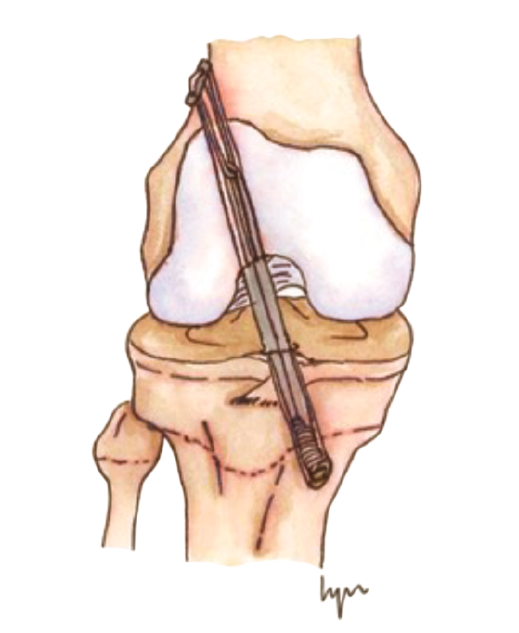

El tratamiento conservador, mediante reposo deportivo y rehabilitación, con una incorporación gradual a la práctica deportiva, pretende recuperar la actividad previa evitando las posibles lesiones fisarias iatrogénicas asociadas a las técnicas de reconstrucción del LCA convencionales, que pudieran producir dismetrías y alteración de los ejes(4,5,6,7,8). Sin embargo, este enfoque subestima las posibles lesiones meniscales y condrales futuras relacionadas con la inestabilidad secundaria. Por otro lado, el tratamiento quirúrgico intenta prevenir estas lesiones meniscales y condrales, secundarias a la inestabilidad que se produce tras la lesión del LCA, asumiendo el riesgo potencial de lesiones fisarias. Atendiendo a estas premisas, en los últimos años se han descrito técnicas específicas para pacientes esqueléticamente inmaduros que minimizan la agresión de la placa fisaria(9,10,11,12,13,14,15,16)(Figura 1).

Figura 1. Esquema de los tipos de reconstrucción del ligamento cruzado anterior (LCA) según la relación con la fisis. A: epifisaria; B: transfisaria.